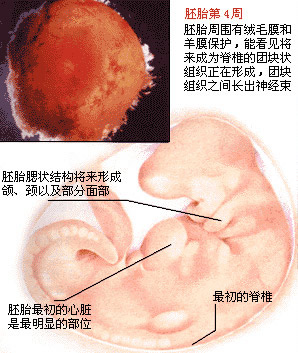

怀孕第 4 周胎儿发育状况

这个时期胚胎已经在子宫内“着床”,或称“植入”。完成着床大概需要 4-5 天,而且必须具备 3 个条件,即透明带在受精后 7 天左右必须消失,使胚泡解脱并与子宫内膜直接接触;子宫内膜增殖分泌旺盛,间质水肿,血管扩张充血;囊泡周围的细胞分化为滋养细胞和合体细胞两层,其中合体细胞能分泌溶解子宫内膜的蛋白分解酶,使胚泡着床。

着床后的胚胎慢慢长大,这时大脑的发育已经开始,受精卵不断地分裂,一部分形成大脑,另一部分则形成神经组织。这时要特别注意加强营养,丰富的营养会给脑细胞和神经系统一个良好的成长环境。